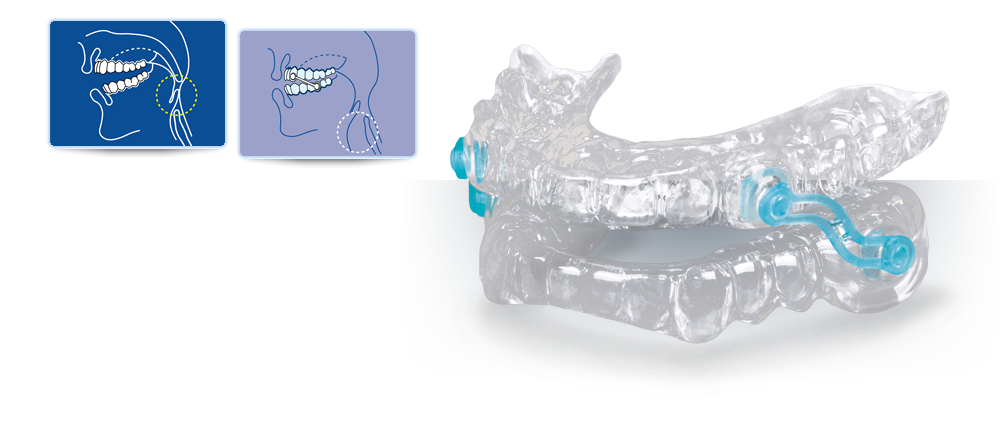

Dispositivos de Avanço Mandibular.

As MADs consistem em equipamentos de vários projectos que fazem com que a mandíbula se mova para frente e caia para baixo. O controle da posição mandibular é garantido por uma ancoragem dentária. As primeiras DAMs foram aplicadas entre o final dos anos 80 e o início dos anos 90 e os primeiros resultados sobre sua eficácia foram relatados no New England Journal of Medicine por Peter George, que publicou um artigo sobre um dispositivo monobloco de acrílico com ganchos de retenção nos elementos dentários.

A propulsão mandibular induz:

- Aumento do diâmetro velo faríngeo, especialmente em sua porção lateral, devido à contiguidade anatómica entre os pilares mandíbula, língua e tonsilar (músculo palatofaríngeo e palatoglosso);

- Aumento da tonificação dos músculos da base da língua, que se afasta da parede posterior da faringe, com consequente redução da tendência à verticalização;